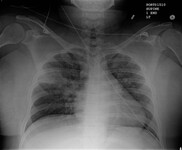

Radiografía de tórax que muestra una adenopatía hiliar bilateral en un paciente con sarcoidosis

De la colección personal del Dr. M.P. Muthiah, Departamento de Medicina Intensiva y Pulmonar y Medicina del Sueño, University of Tennessee